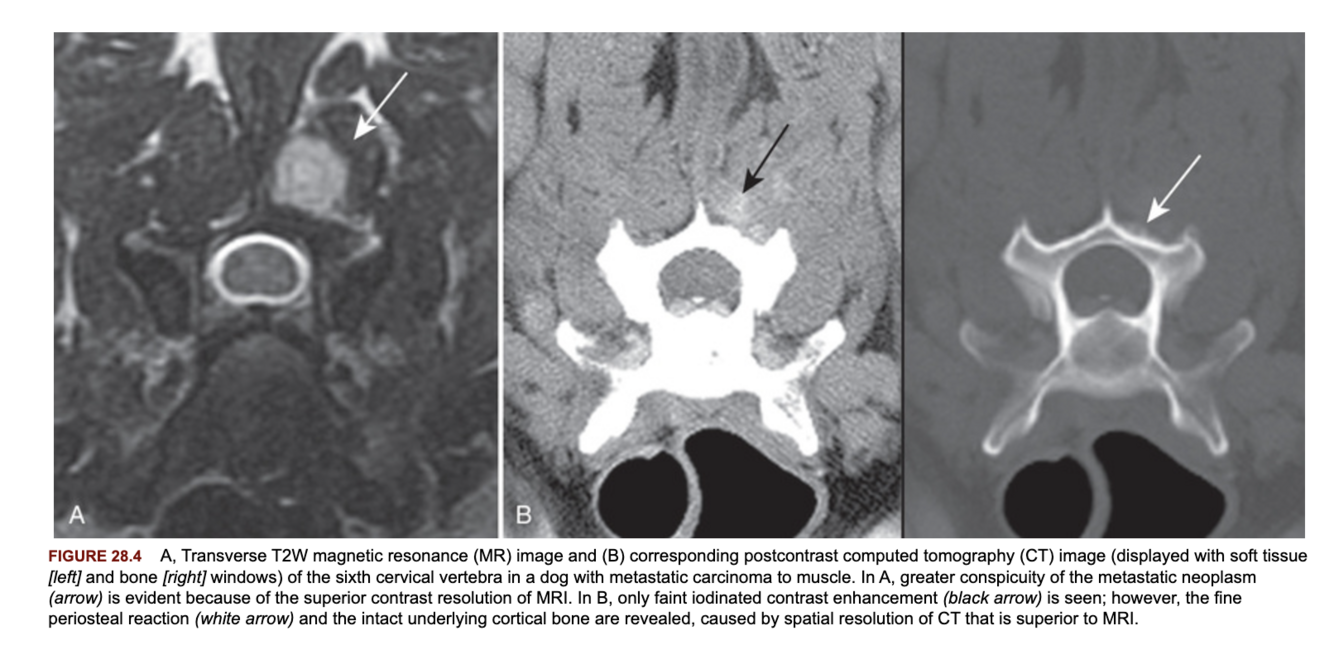

Does CT or MRI have better spatial and contrast resolution?

CT has better spatial resolution, MRI has better contrast resolution

Which imaging modality has the highest spatial resolution?

Radiographs, then CT, then MRI.